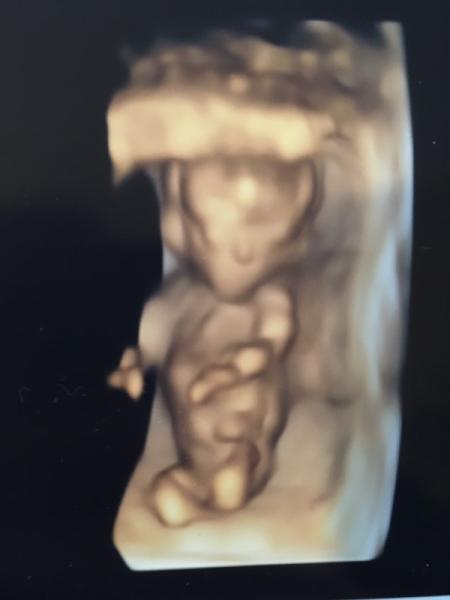

Huhu Waren Dienstag auch zum Ersttrimesterscreening. Laut Ultraschall alles unauffällig. Morgen kriege ich wohl den Anruf mit der Auswertung vom bluttest und kriege die Wahrscheinlichkeit mitgeteilt. Echt aufregend! Haben auch zwei Fotos mitbekommen...Auf dem einen fragt man sich: „Hat es keinen Mund?“ Auf dem anderen: „Was kommt den Krümel da aus dem Kopf? Ein Finger? Das sieht so groß aus...?“ Und was ist das für ein Knochen (?) da am Oberkiefer? Wenn die Zunge ein Knochen wäre, könnte man meinen, es streckt sie raus

2. Bild